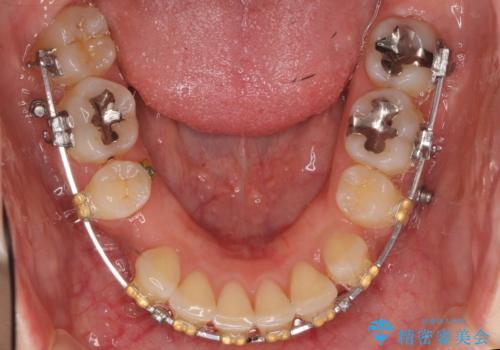

- 矯正装置

- 審美装置

- 治療計画

- 前歯を下げたいと来院。

初めは、上だけ抜歯しましたが、もう少し口元を下げたいとのことで追加で下顎を抜歯しました。

年齢の割に歯が動きにくかったこともあり、また、追加で抜歯して結果として時間がかかってしまいました。口元が大きく下がり、結果には満足していただけました。